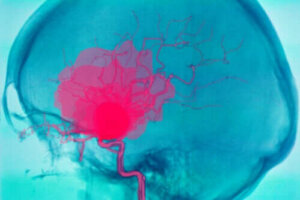

Aivoverenvuoto tarkoittaa hengenvaarallista tilaa, joka voi koitua ihmisen kohtaloksi. Tällöin aivoissa tapahtuu verenvuotoa, minkä vuoksi muut kehonosat kärsivät hapen puutteesta.

Kuten artikkelin alussa kerroimme, aivoverenvuoto tarkoittaa aivoissa tapahtuvaa verenvuotoa. Usein sen seurauksena on yhtäkkisiä neurologisia ongelmia ja joissakin tapauksissa koomaan vajoaminen.

Tämä johtuu siitä, että aivojen muut osat eivät saa tarpeeksi verta, koska veri ei pääse jatkamaan matkaansa verisuonissa. On tärkeää osata erottaa intraserebraalinen eli aivoverenvuoto sekä intrakraniaalinen eli kovakalvonalainen verenvuoto toisistaan.

Kovakalvonalainen verenvuoto tarkoittaa kallonsisäistä verenvuotoa, toisin kuin intraserebraalinen verenvuoto tarkoittaa aivokudoksessa tapahtuvaa verenvuotoa. Muita verenvuotoja ovat esimerkiksi intraventrikulaarinen, subaraknoidaalinen eli aivokalvonalainen, subduraalinen eli krooninen kovakalvonalainen sekä epiduraalinen vuoto.

Aivoverenvuoto on yksi päääasiallisimmista aivohalvauksen aiheuttajista. Asiantuntijoiden arvioiden mukaan, noin 15 % aivoinfarkteista johtuu aivoverenvuodosta. Lisäksi aivoverenvuotoon liittyy korkea kuolleisuus, etenkin ensimmäisten päivien aikana.